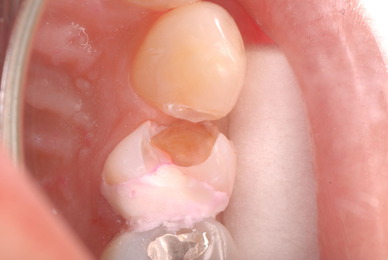

歯周病の疑いで東京のかなり遠方の方が来院されました。

驚くべきことですが、定期検診は受けていたそうです。しかしながら歯周病の指摘は受けたことがないそうです。

何故か?定期検診が虫歯のチェックのみになり、又肝心の歯周病の検査や歯周病の部分の予防や治療のためのブラシの使い方などを学んだ事がないのです。